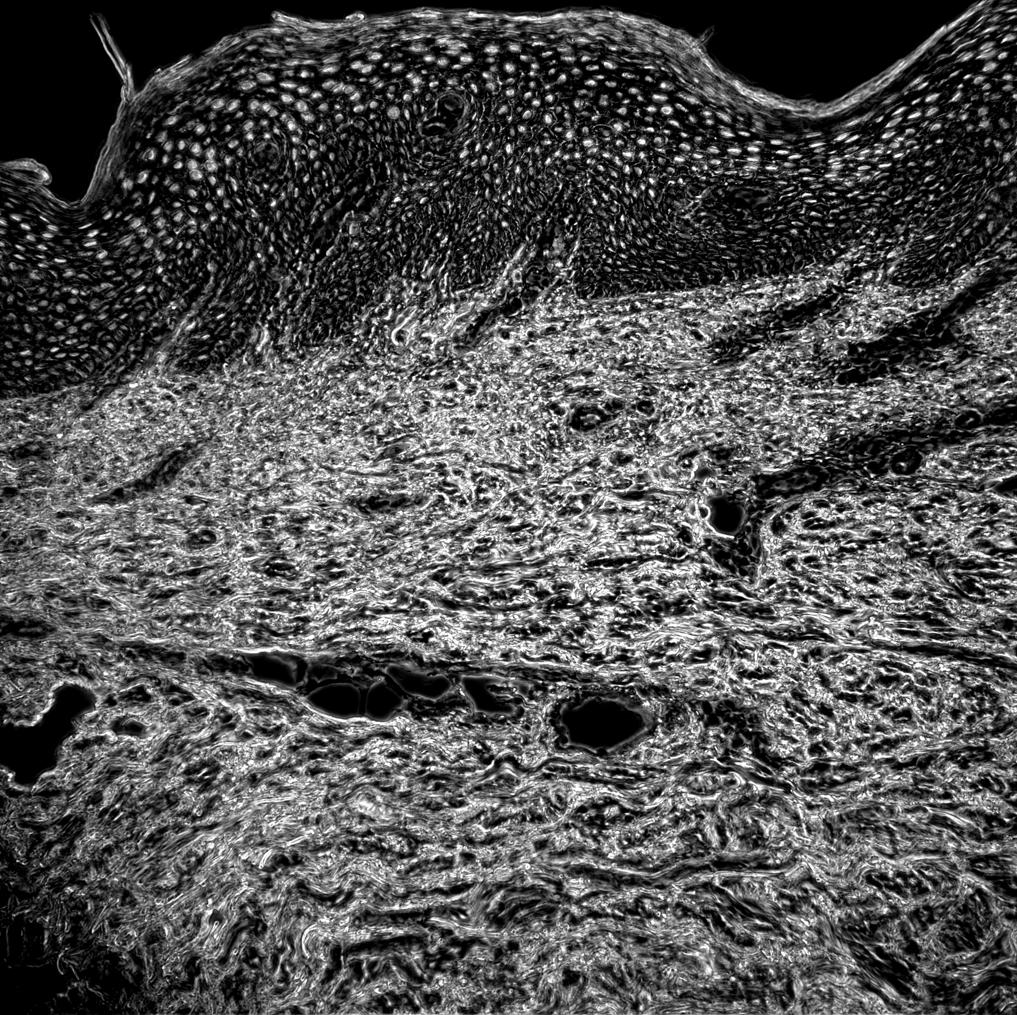

Phase contrast image

Keratinocytes

Collagen

Vessels

Psoriatic Skin

Human tissue section

Autoimmune loop